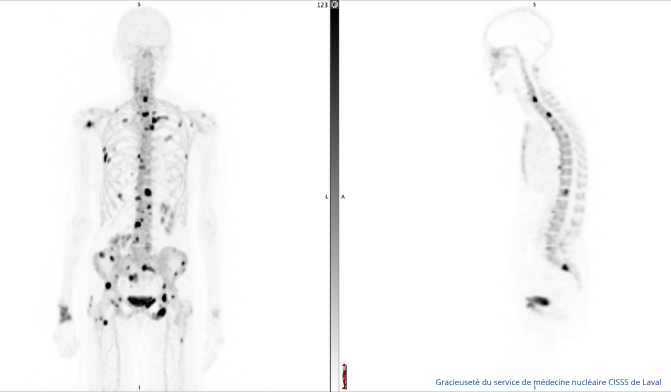

L’injection de NaF Plus est indiquée comme accessoire à la tomographie par émission de positons (TEP) pour la détection des zones d’ostéogenèse altérée associées aux métastases osseuses.